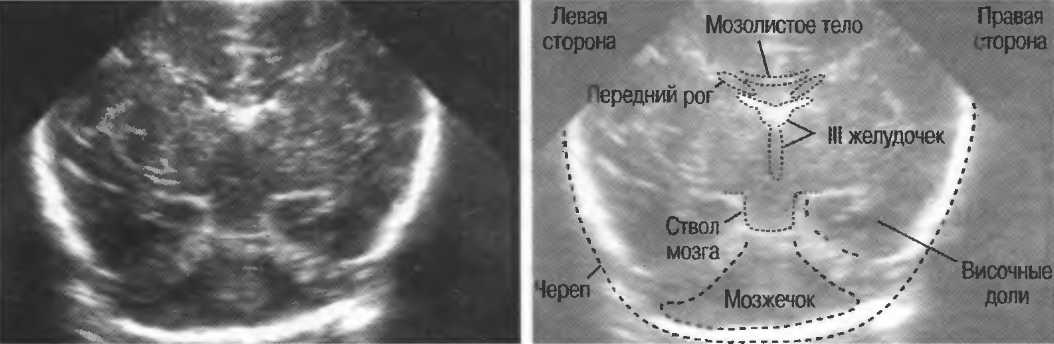

3. Ультразвуковые исследования в педиатрии. Для детей необходим датчик с частотой 5 МГц с глубиной фокусировки на 5-7 см. При исследовании мозга новорожденного используется секторный датчик с частотой 7,5 МГц с глубиной фокусировки на 4-5 см (этот датчик также используется для исследования яичек и структур шеи у взрослых).